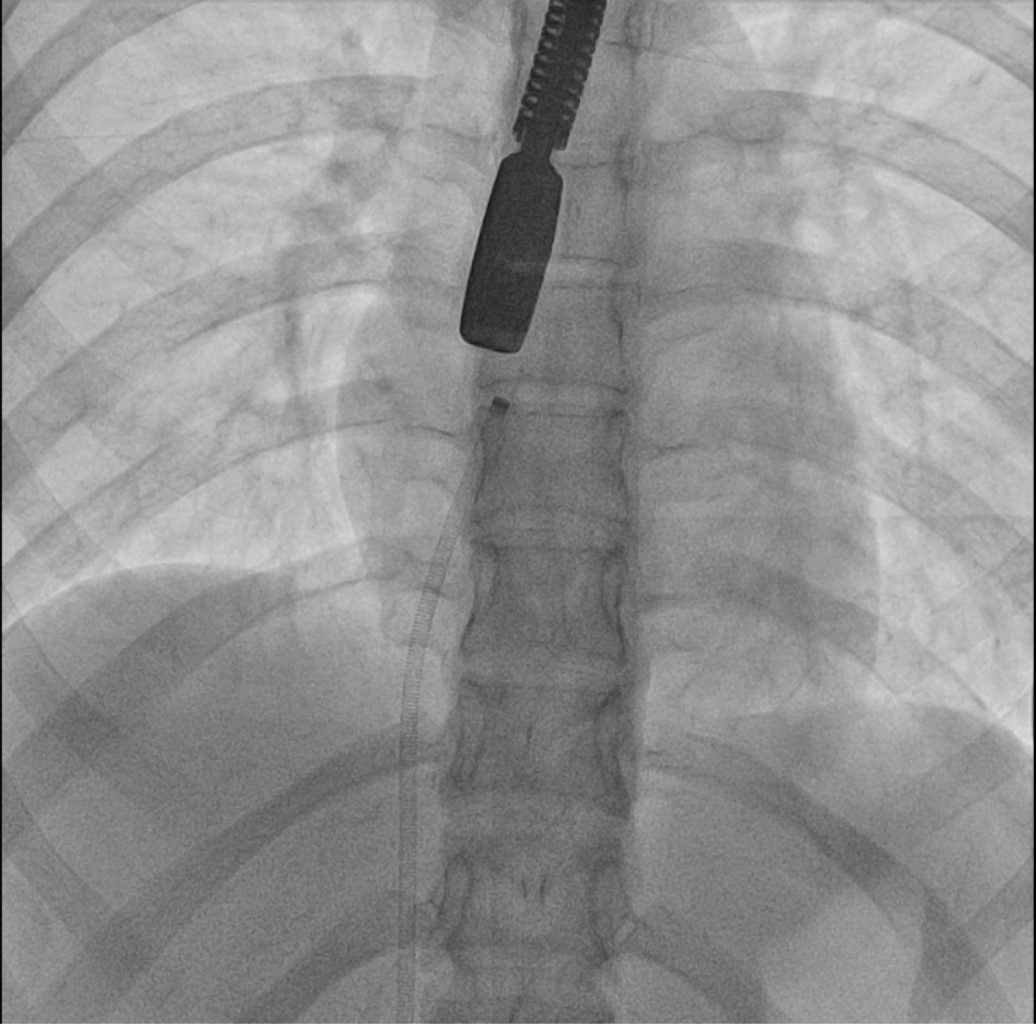

Introducción: el sarcoma mieloide, también conocido como sarcoma granulocítico o cloroma, es una neoplasia maligna resultante de la infiltración de células mieloides inmaduras en tejidos extramedulares, con una incidencia estimada de 2.5-9.1% en pacientes con leucemia mieloide aguda (LMA). El corazón es un sitio poco común de aparición (< 1%). Actualmente, no existen pautas diagnósticas ni de tratamiento firmemente establecidas para esta condición. Caso clínico: paciente femenino de 21 años con antecedente de leucemia mieloide aguda (translocación 9:11), diagnosticada a los 16 años. Tras recibir quimioterapia logró la remisión en octubre de 2019. Fue referida para seguimiento en diciembre de 2021, presentando síndrome consuntivo, palpitaciones y disnea (NYHA II). Conclusiones: este caso resalta la rareza del sarcoma mieloide cardiaco y subraya la necesidad de utilizar imagenología multimodal en el diagnóstico y seguimiento. Además, destaca la relevancia de establecer rutas asistenciales especializadas con una perspectiva cardio-onco-hematológica en México.

Figura 2